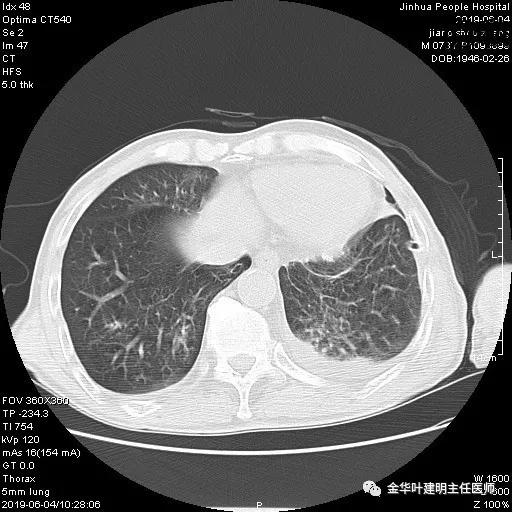

6.4上午:24小时引流出血性乳糜液1800毫升。是否再次手术进行右进胸胸导管结扎,抑或继续保守治疗非常纠结!压力非常大!!多方讨论会诊无法取得一致意见,但一般认为,引流量在1000毫升以上宜积极手术。情况与浙二医院范军强教授联系,请求指导,范教授认为左侧肺手术,损伤胸导管主干的机会较小,多数可保守治疗而愈。在他们的病例中,也有结扎胸导管后引流量仍无减少,效果并不能完全保证。建议可以考虑胸管夹管观察(因为淋巴管压力低,予以适当的压力,漏出量可能会明显减少),同时继续禁食,并静脉营养支持,引流管口可能会有渗液,注意更换敷料。与家属充分沟通后决定试夹管;这天血色素9.0 g/L;胸部CT复查示:

夹管情况下,于6.5复查胸片:

感觉左肺密度还可以,肺没有被全部压萎陷,积液有,但不是特别多。